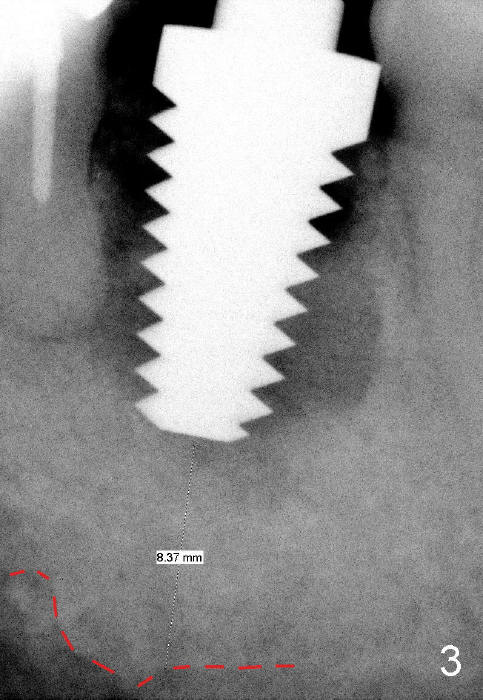

When the tooth is extracted, the socket is extremely large. The largest tapered tap (8x17 mm) basically drops into the socket; it is not stable in the socket (Fig.3). It appears necessary to engage into the nascent bone, which is 8.37 mm long.